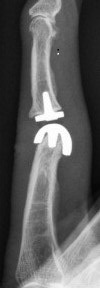

Blickfang ist hier das x-förmige Implantat zur Versteifung eines schmerzhaften und ehemals deformierten Endgelenkes.

Im Mittelgelenk fällt ein flauer "Schatten" von einem Kunstgelenk aus Silikon (Silikonendoprothese) auf.